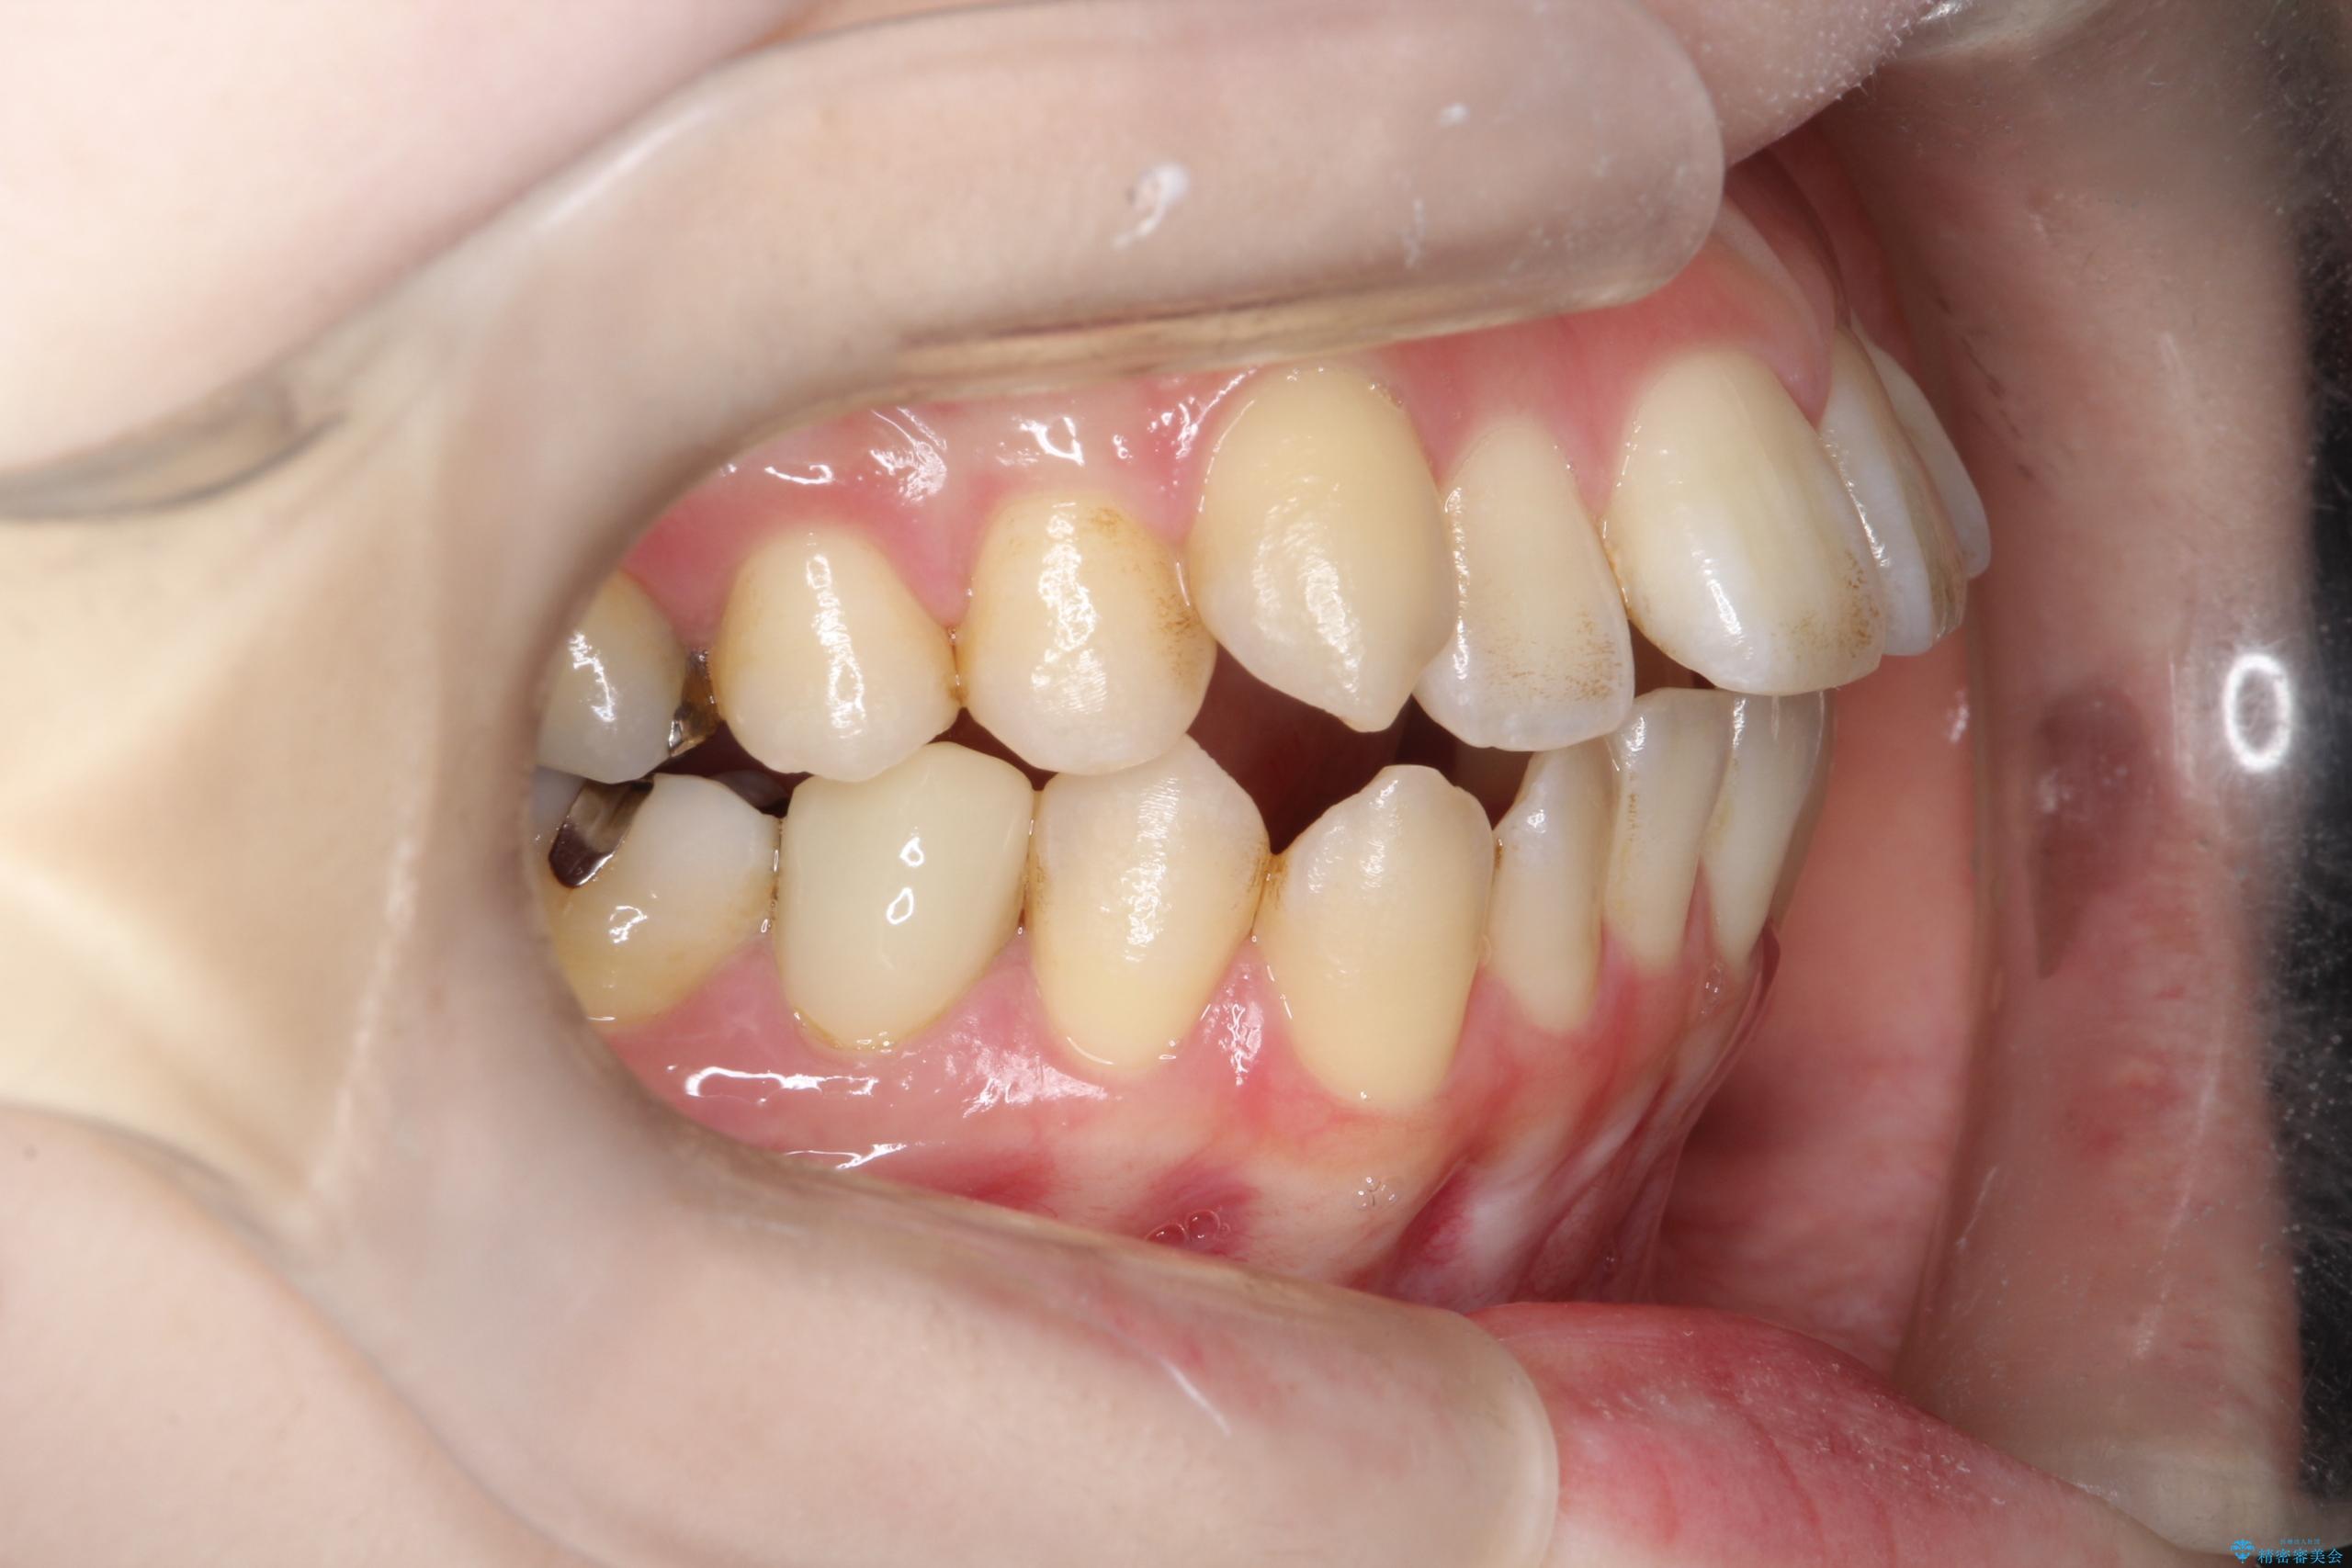

- 開咬と歯のデコボコ(叢生)、八重歯を主訴にご来院された患者様です。

矯正の精密検査の結果、上顎左右4番および下顎左右5番の計4本を抜歯し、ワイヤー矯正(クリア装置)にて治療を行いました。

虫歯があったので、虫歯治療は矯正前に行っています。